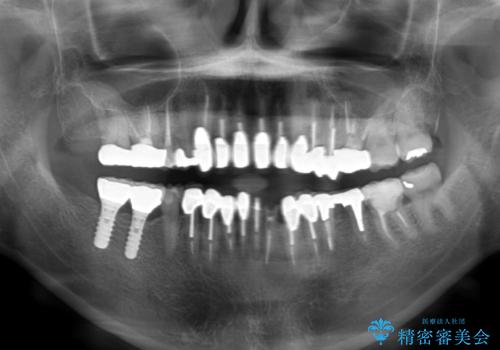

- 下顎の前歯に激痛を覚えて来院された患者様です。

取り急ぎ下顎前歯数歯の根管治療を、銀座しらゆり歯科医院長の林先生にお願いし、それ以外に気になっている、不自然な色調のクラウン、金属部分が見えてブラッシングがしにくいインプラント補綴、口元の突出感、出血のしやすい歯周ポケットなど、全てを解決するための治療を行うこととしました。